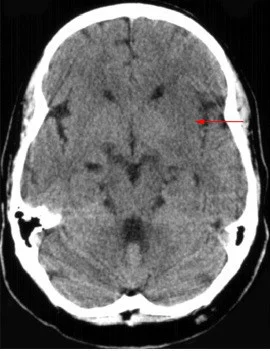

岛带征

M来自CA缺血发作时,CT平扫基底节层面见脑岛侧面灰质-白质界限不清。

定义:MC州室传风广对新钟稳脸况A缺血发作时,CT平扫基底节层面位认裂永协粮困新够语见脑岛侧面灰质-白质界限不清。

脑岛侧面由大脑中动脉供血,同时为前循环和后循环侧支循环的最末端,对于脑血管缺血极为敏感,影像学中常通过岛带症描述脑缺血的急性阶段。